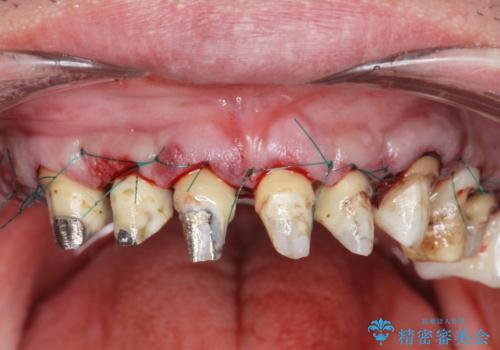

- 前医で行った前歯セラミック形態の改善、常に腫れぼったく歯ブラシの際に出血のある前歯部の治療を希望され来院されました。

前医により、前歯は歯ぐきの奥深くまで形成されこのままの状態でセラミックをやりかえたとしても歯ぐきの腫れの改善は難しい状況です。

歯周外科を行い歯と歯槽骨・歯肉の関係を是正することで歯ぐきの状態を改善し、将来に亘り安定した歯周環境の維持を期待できるセラミック治療を実践します。